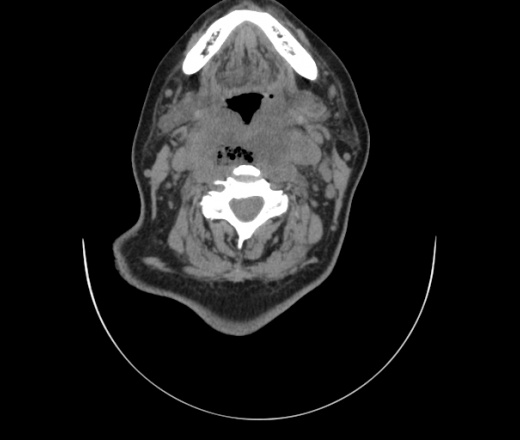

Женщина поступила в х/о спустя 4 дня после того как при употреблении карася подавилась костью.

Наличие газа в средостении на протяжении тел С2-С6 (медиастинальна эмфизема); рыбная кость на уровне тела С6.

При всем уважении, но говорить о медиастинальной эмфиземе, оценивая мягкие ткани шеи, как-то слишком резко. На мой взгляд, это ретрофарингеальное пространство.

Эвакуировали почти 100мл гноя. Но кость не смогли найти. Думаю что она даст дальнейшее ослоднение. Эндоскопически за черпалонадгортаной звязкой не смогли зайти в пищевод, все мягкие ткани отечные, просвет пищевода сдавлен. По всей видимости параэзофагеальная клетчака тоже задействована. Эмпиема, если ее можно так назвать, незнаю как правильно дошла до уровня яремной вырезки. Чем закончиться напишу. Ждем медиастинита.

Флегмона заглоточного пространства шеи, только операция, флегмоны вскрывают. Риск медиастинита.

Согласен с Вами; конечно, наличие газа в клетчатке ретрофарингеального пространства (затмение с опечаткой..). К сожалению, процесс "продвигается" к медиастиниту. Но почему никто, не отмечает наличие рыб. кости; или это для Всех очевидно?

Так вы уже отметили. Хотя ориентировал бы не скелетотопически, а на перстнечерпаловидный сустав.

Кость то мы сразу выявили, размеры где то 17*2мм, но ее так и не получается найти в этой каше